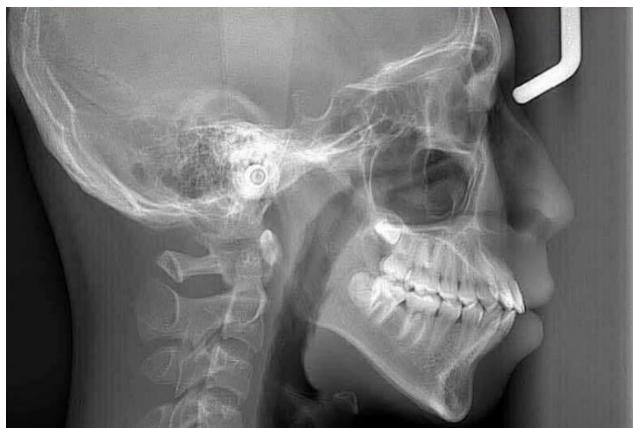

Figure 4: Pre-Treatment Lateral Cephalometric Radiograph

Cephalometric analysis according to the Ricketts system revealed a mild skeletal Class II relationship, with a facial convexity of $3.4 \mathrm{~mm}$ [15]. The mandible was mildly retrusive relative to the cranial base, as indicated by a facial depth of $85.8^{\circ}$, while the maxilla demonstrated a relatively neutral position with a maxillary depth of $88.9^{\circ}$ [15,16].

Vertical analysis demonstrated a pronounced vertical growth pattern, with an increased FMA of $36.7^{\circ}$, an increased lower facial height (LFH) of $48^{\circ}$ (compared with the normal range of $45 - 46^{\circ}$ ), and a reduced facial taper of $57.5^{\circ}$ relative to the average value of approximately $68^{\circ}$ [3,15]. These findings reflect a tendency toward clockwise mandibular rotation and vertical facial imbalance.

Dentally, both maxillary and mandibular incisors exhibited markedly increased proclination and protrusion compared with physiological norms (maxillary incisors: protrusion 13.3 mm, inclination $41.6^{\circ}$; mandibular incisors: protrusion 10.7 mm, inclination $36.1^{\circ}$ [6,15]. Overall, this case represents severe bimaxillary incisor protrusion on a background of mild skeletal Class II malocclusion with a high-angle growth pattern, accompanied by an unfavorable biological risk factor characterized by the close proximity of the mandibular incisor roots to the labial cortical plate [10-12].